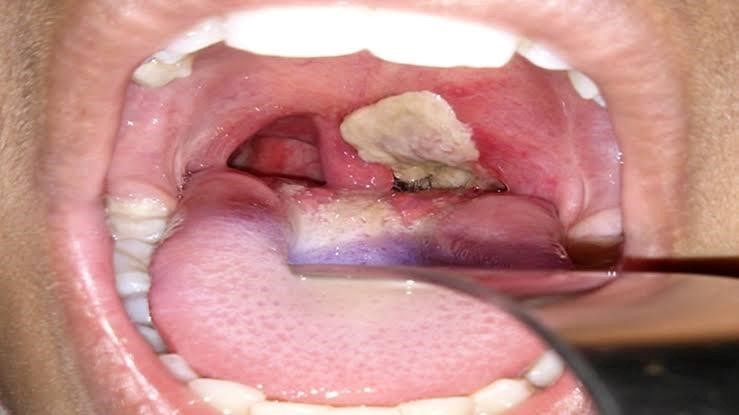

C- Advocate reports that diphtheria, a highly contagious bacterial infection caused by Corynebacterium diphtheriae, broke out in Imo, with an index case reported in Mbutu, Aboh Mbaise council area of the state.

He said that with 10 fatalities already recorded according to available statistics, it was imperative to restrict and contain the spread of the disease to prevent a possible “national disaster “, as the airport “sits very close to Aboh Mbaise”.